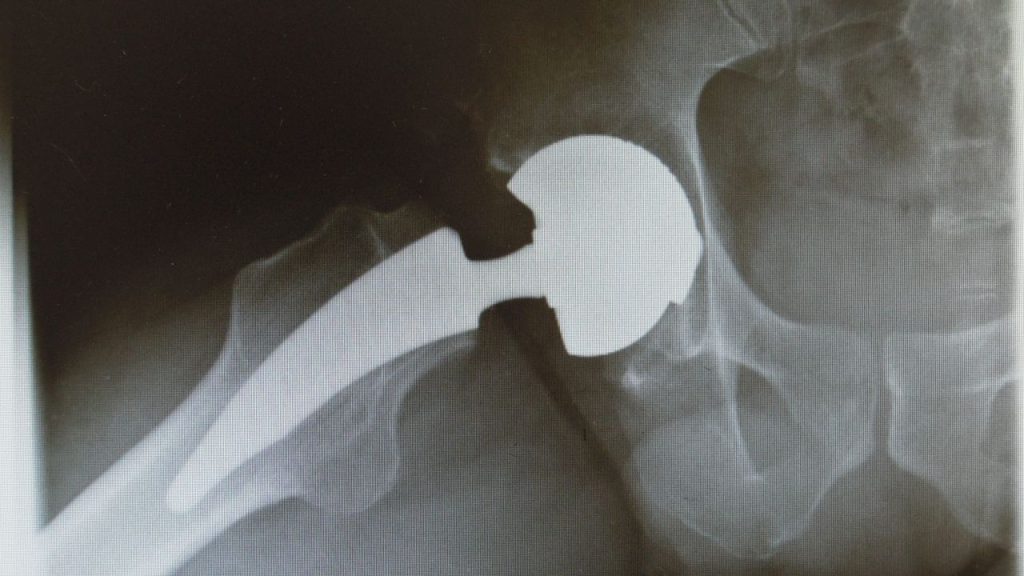

Chirurgia Protesica Mini-Invasiva

• Protesi di anca (accesso mini-invasivo)

• Protesi di ginocchio (mono/bi/tricompartimentale)

• Protesi di spalla (anatomiche e inverse)

• Protesi di caviglia (mini-invasive, con carico precoce)